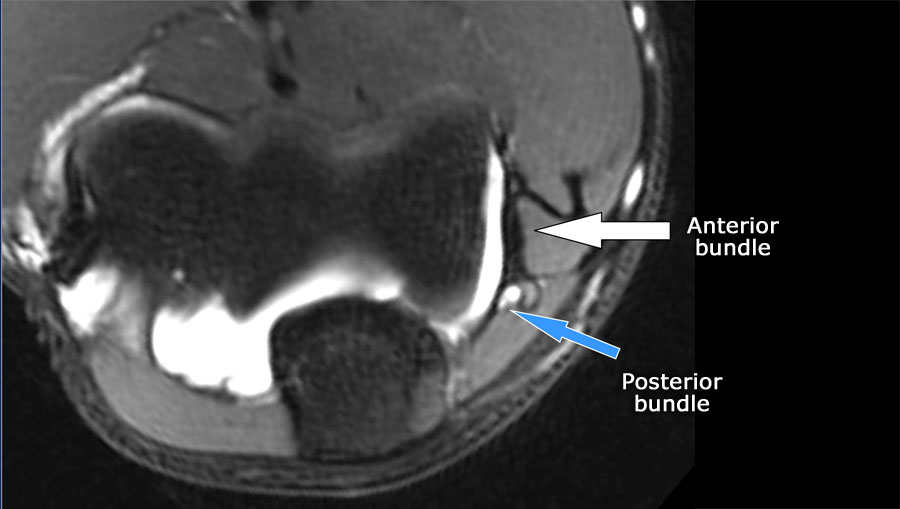

Luôn sử dụng hình ảnh mặt cắt ngang (axial) khi nghiên cứu các dây chằng, đặc biệt là dây chằng bên trụ (UCL).

Scroll through the images.

- Nếu bạn nhìn vào mỏm trên lồi cầu trong, bạn sẽ nhận thấy bó sau như một cấu trúc mỏng (mũi tên xanh).

- Notice the ulnar nerve sitting in the cubital tunnel.

- The posterior bundle forms the floor of the cubital tunnel.

- A retinaculum covers the cubital tunnel.

- Lưu ý rằng bó trước dày hơn nhiều (mũi tên trắng).

- Bạn có thể thấy sự khác biệt giữa dây chằng trước và dây chằng sau mặc dù chúng tạo thành một dây chằng duy nhất.

- Khi đi về phía xa, chúng ta sẽ thấy chúng hợp nhất lại để bám vào củ sublime.